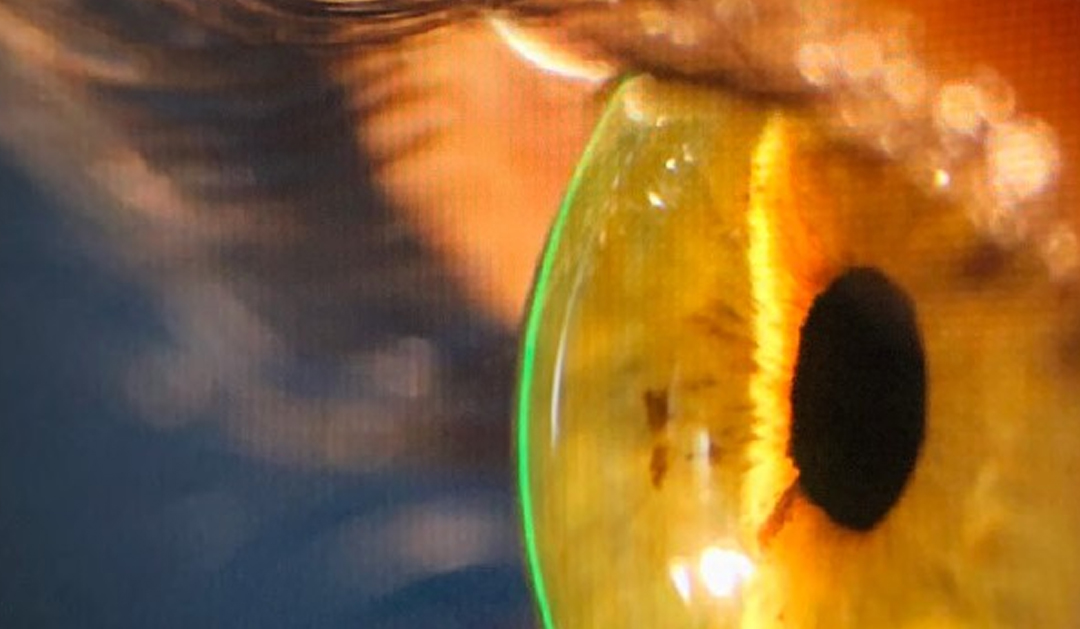

CONTROL DE ABERRACIONES CON LENTES DE APOYO ESCLERAL

Luis Izquierdo MD,Oftalmólogo Edward Carmona, O.D.NCLE-AC – FSLS Los errores refractivos como la hipermetropía, miopía y astigmatismo son condiciones conocidos como aberraciones de bajo orden. Estos generalmente se corrigen con gafas o lentes de contacto...